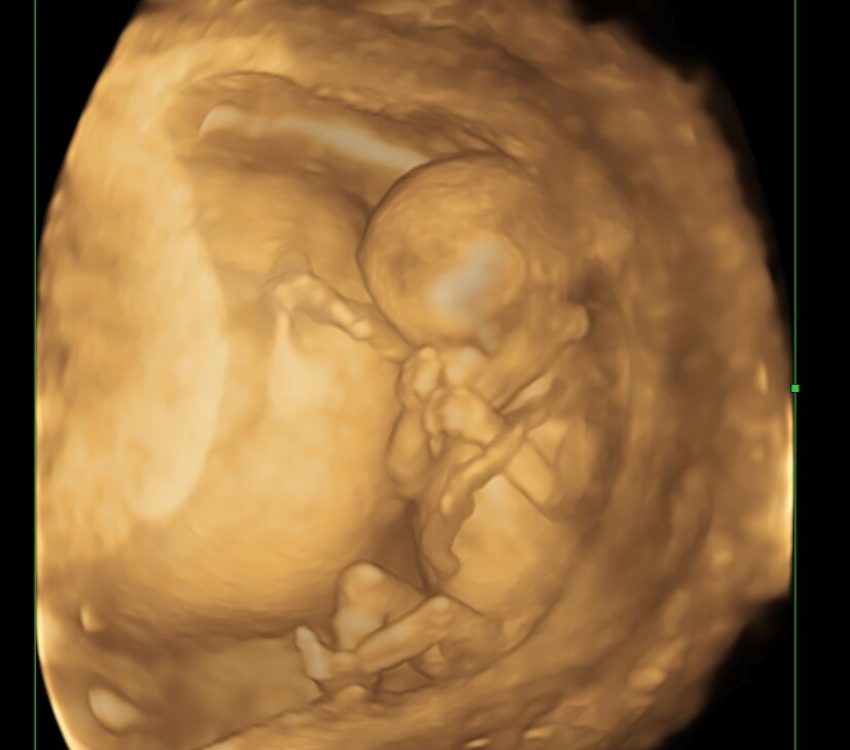

Fetal Growth Scan (28–32 Weeks GA)

Your Complete Guide to Fetal 3D/4d Growth Scan in Kolkata at NESA Institute of Fetal Medicine Are you looking for

Long term training program

NESA’s Fellowship in Fetal Medicine & Ultrasound provides advanced training for Obstetrics and Gynecology (OB-GYN) physicians who wish to specialize in fetal imaging, diagnostics, and high-risk pregnancy management. Fellows gain in-depth exposure to 2D, 3D/4D, and Doppler imaging, invasive fetal therapies, and perinatal counseling. The program blends hands-on training, academic rigor, and research opportunities, preparing participants for leadership roles in fetal medicine.